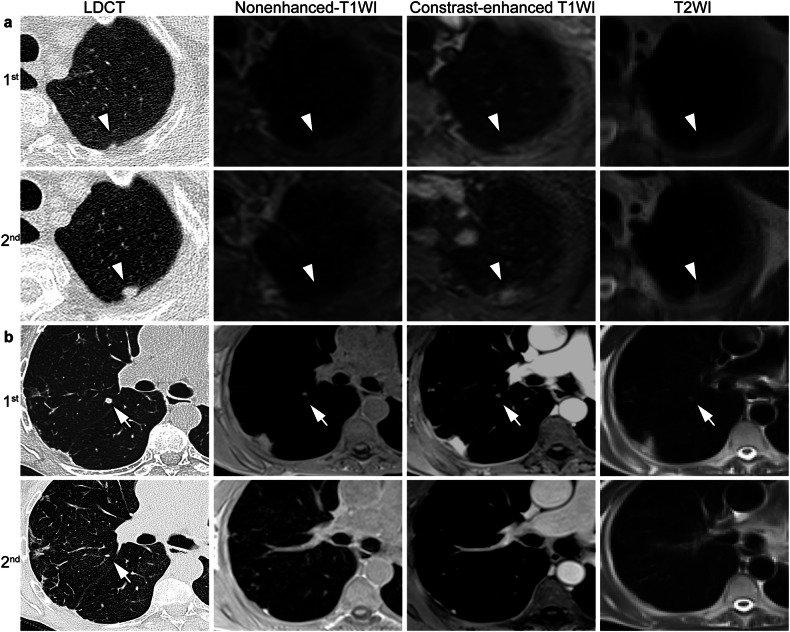

Materials and methods: 239 participants (63.9 ± 8.4 years, 43-82 years) at risk of or with COPD GOLDI-IV from 16 centers prospectively underwent two rounds of same-day low-dose computed tomography (LDCT1&2) and MRI1&2 at an interval of three years in the nationwide COSYCONET trial. All exams were independently assessed for incidental pulmonary nodules in a standardized fashion by two blinded readers, incl. axis measurements and Lung-RADS categorization, with consensual LDCT results serving as the standard of reference. A change in diameter ≥ 2 mm was rated as progress. 11 patients underwent surgery for suspicious nodules after the first round.

Results: Two hundred twenty-four of two hundred forty nodules (93.3%) persisted from LDCT1 to LDCT2, with a sensitivity of MRI2 of 82.8% and 81.5% for readers 1 and 2, respectively. Agreement in Lung-RADS categories between LDCT2 and MRI2 was substantial in per-nodule (κ = 0.62-0.70) and excellent in a per-patient (κ = 0.86-0.88) approach for both readers, respectively. Concordance between LDCT2 and MRI2 for growth was excellent to almost perfect (κ = 0.88-1.0). The accuracy of LDCT1 and MRI1 for lung cancer was 87.5%. Lung-RADS ≥ 3 category on MRI1 had higher accuracy for predicting progress (23.1% and 21.4%, respectively) than LDCT1 (15.8%).

Conclusion: Compared to LDCT, MRI shows similar capabilities for the longitudinal evaluation of incidental nodules in heavy smokers. Decision-making for nodule management guided by Lung-RADS seems feasible based on longitudinal MRI.